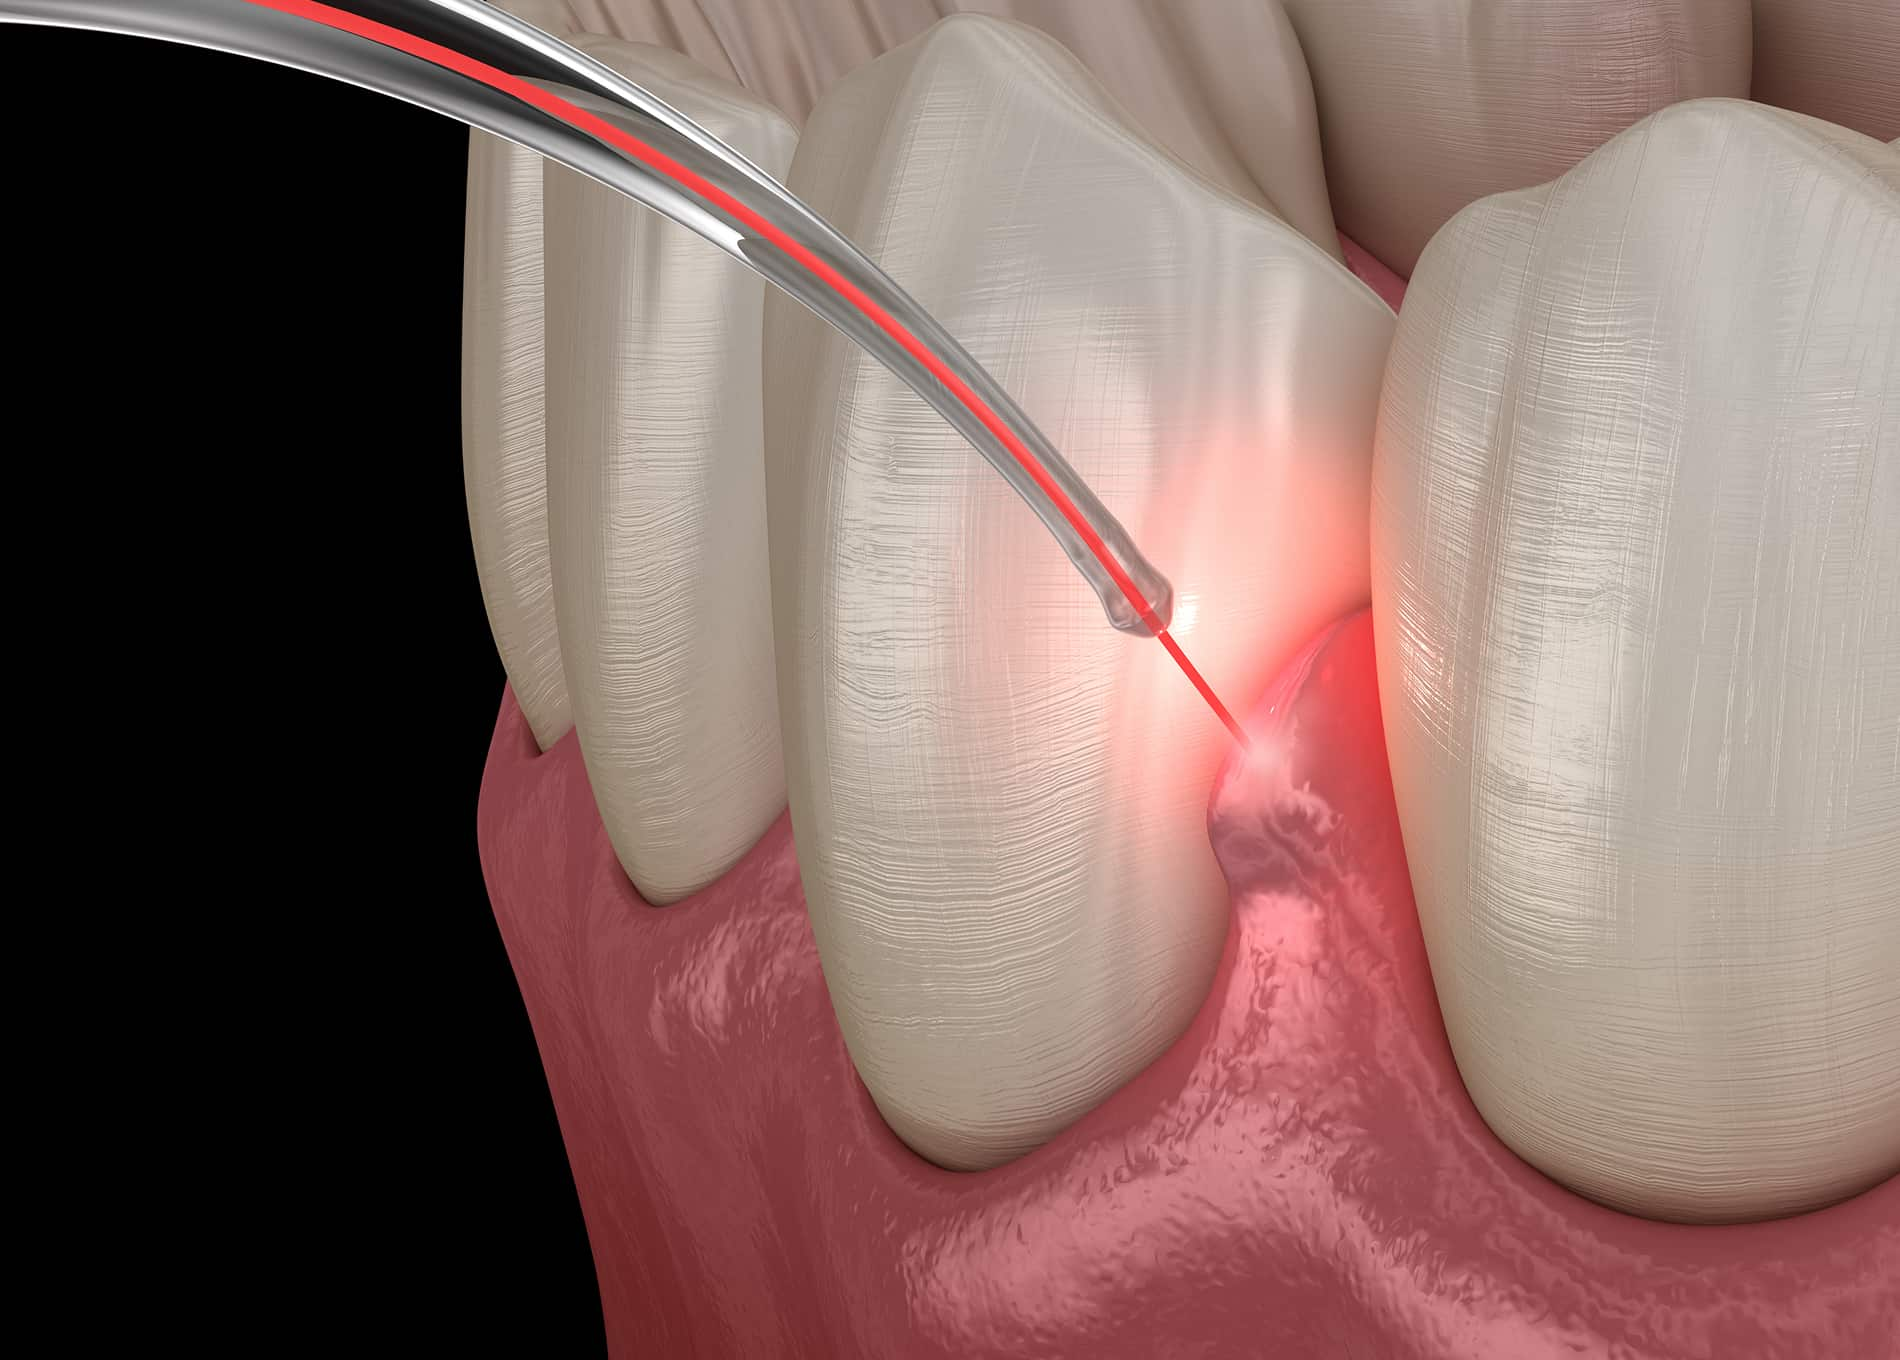

Gum disease, or periodontal disease, begins with inflammation and can progress to affect the bone and tissues supporting your teeth. At Mantis Dentistry & Implant Center, we offer advanced treatments to halt its progression and restore your oral health. From deep cleanings to laser therapy, our care is tailored to your unique needs, delivered with precision and compassion.